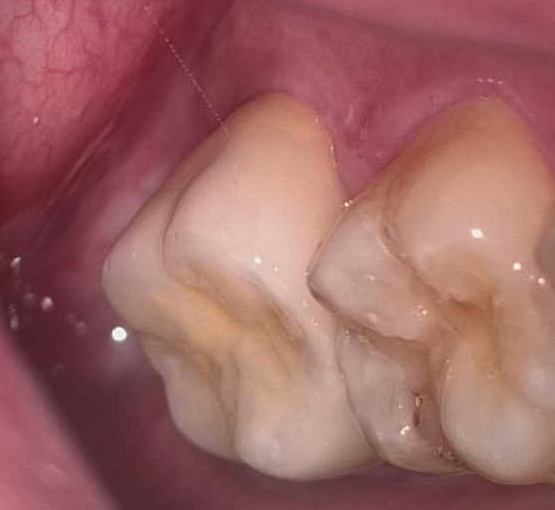

その後も安定した状態が確認できたため、

最終補綴としてセラミッククラウンを装着しました。

現在も問題なく機能しており、

安定した状態を維持しています。